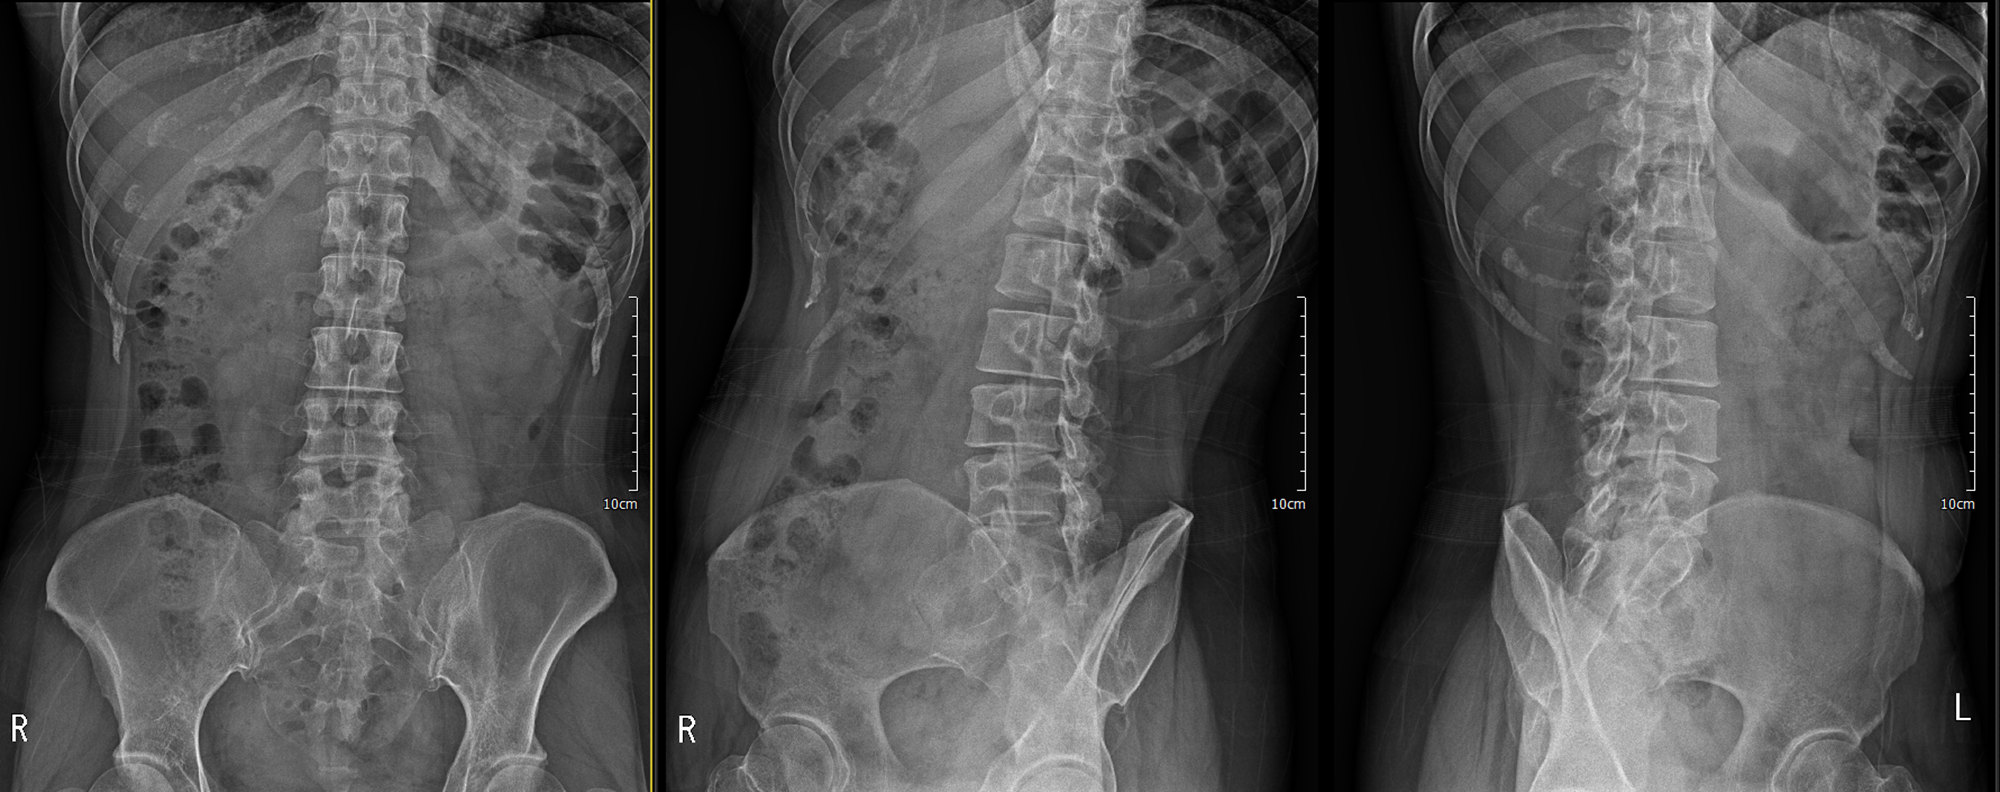

이번에 촬영한 x ray

디스크 간격이 좁은 곳 확인

L3/4 4/5